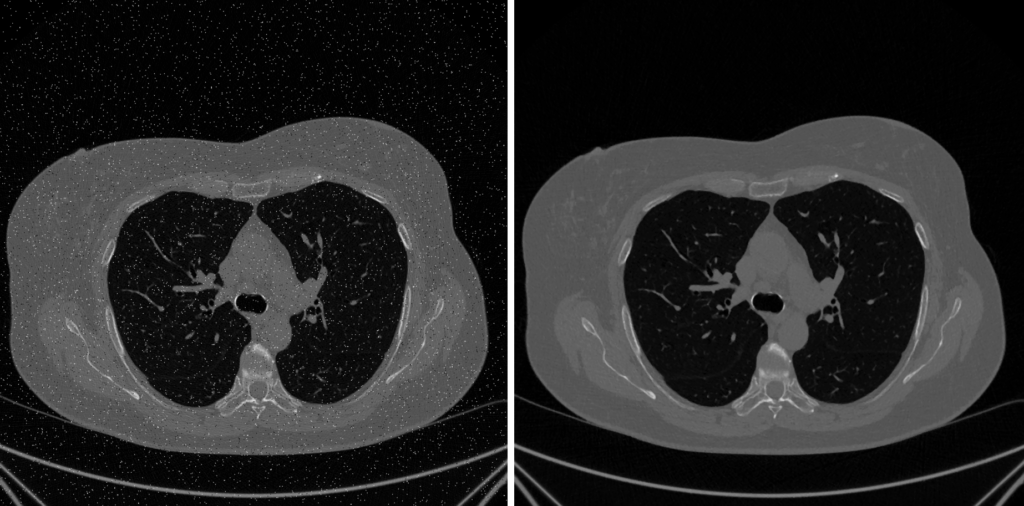

4. Fase 3: Denoising e Sharpening

Dopo aver corretto gli artefatti sistematici, l’immagine è corretta, ma non ancora pulita. Può essere ancora affetta da rumore casuale (elettronico o statistico), che oscura i dettagli fini e complica le analisi successive come la segmentazione.

Esploriamo ora due operazioni complementari e in apparente conflitto: il Denoising (ridurre il rumore) e lo Sharpening (evidenziare i bordi).

1. Denoising: Smussare il Rumore, Preservare il Segnale

L’obiettivo è sopprimere il rumore senza distruggere i bordi e le texture reali dell’immagine.

Filtri Locali Semplici

- Filtro Gaussiano: L’approccio classico. Sostituisce ogni pixel con una media pesata dei suoi vicini.

- Pro: Molto efficace nel ridurre il rumore gaussiano.

Contro: Sfoca tutto, inclusi i bordi e i dettagli diagnostici.

- Filtro Mediano : è un filtro non lineare eccellente per la riduzione del rumore impulsivo (sale e pepe), mantenendo i dettagli dell’immagine

- Pro: E’ stremamente efficace nel rimuovere picchi isolati di rumore (“sale e pepe”) e per sostituire pixel eccessivamente luminosi o scuri anomali (hot/dead pixels).

- Contro:Tende a sfocare leggermente i dettagli minuti e le texture sottili ed è meno efficace contro il rumore gaussiano rispetto ad altri filtri.

Filtri Edge-Preserving

- Filtro Bilaterale è un miglioramento sofisticato del filtro Gaussiano che utilizza una media pesata basata su due criteri fondamental: La Vicinanza Spazialeper cui i pixel più vicini al centro del calcolo ricevono un peso maggiore e la Somiglianza di Intensità dove I pixel con un valore cromatico o di intensità simile ricevono anch’essi un peso maggiore

- Pro: Conservazione dei Bordi e Qualità Visiva Superiore

- Contro: Complessità Computazionale; Selezione dei Parametri per il dominio spaziale e uno per il dominio di intensità può richiedere tentativi ed errori per ottimizzare il risultato; Introduzione di Artefatti se i parametri non sono scelti correttamente.

- Non-Local Means (NLM): Sfrutta la ridondanza presente nell’immagine per il denoising. Per pulire un pixel, cerca “patch” simili in tutta l’immagine (approccio non-locale), non limitandosi all’area circostante. Il nuovo valore del pixel è una media pesata dei pixel centrali di tutte le patch simili trovate.

- Pro: Denoising eccellente preservando le texture fini.

- Contro: Alta complessità computazionale e lentezza.